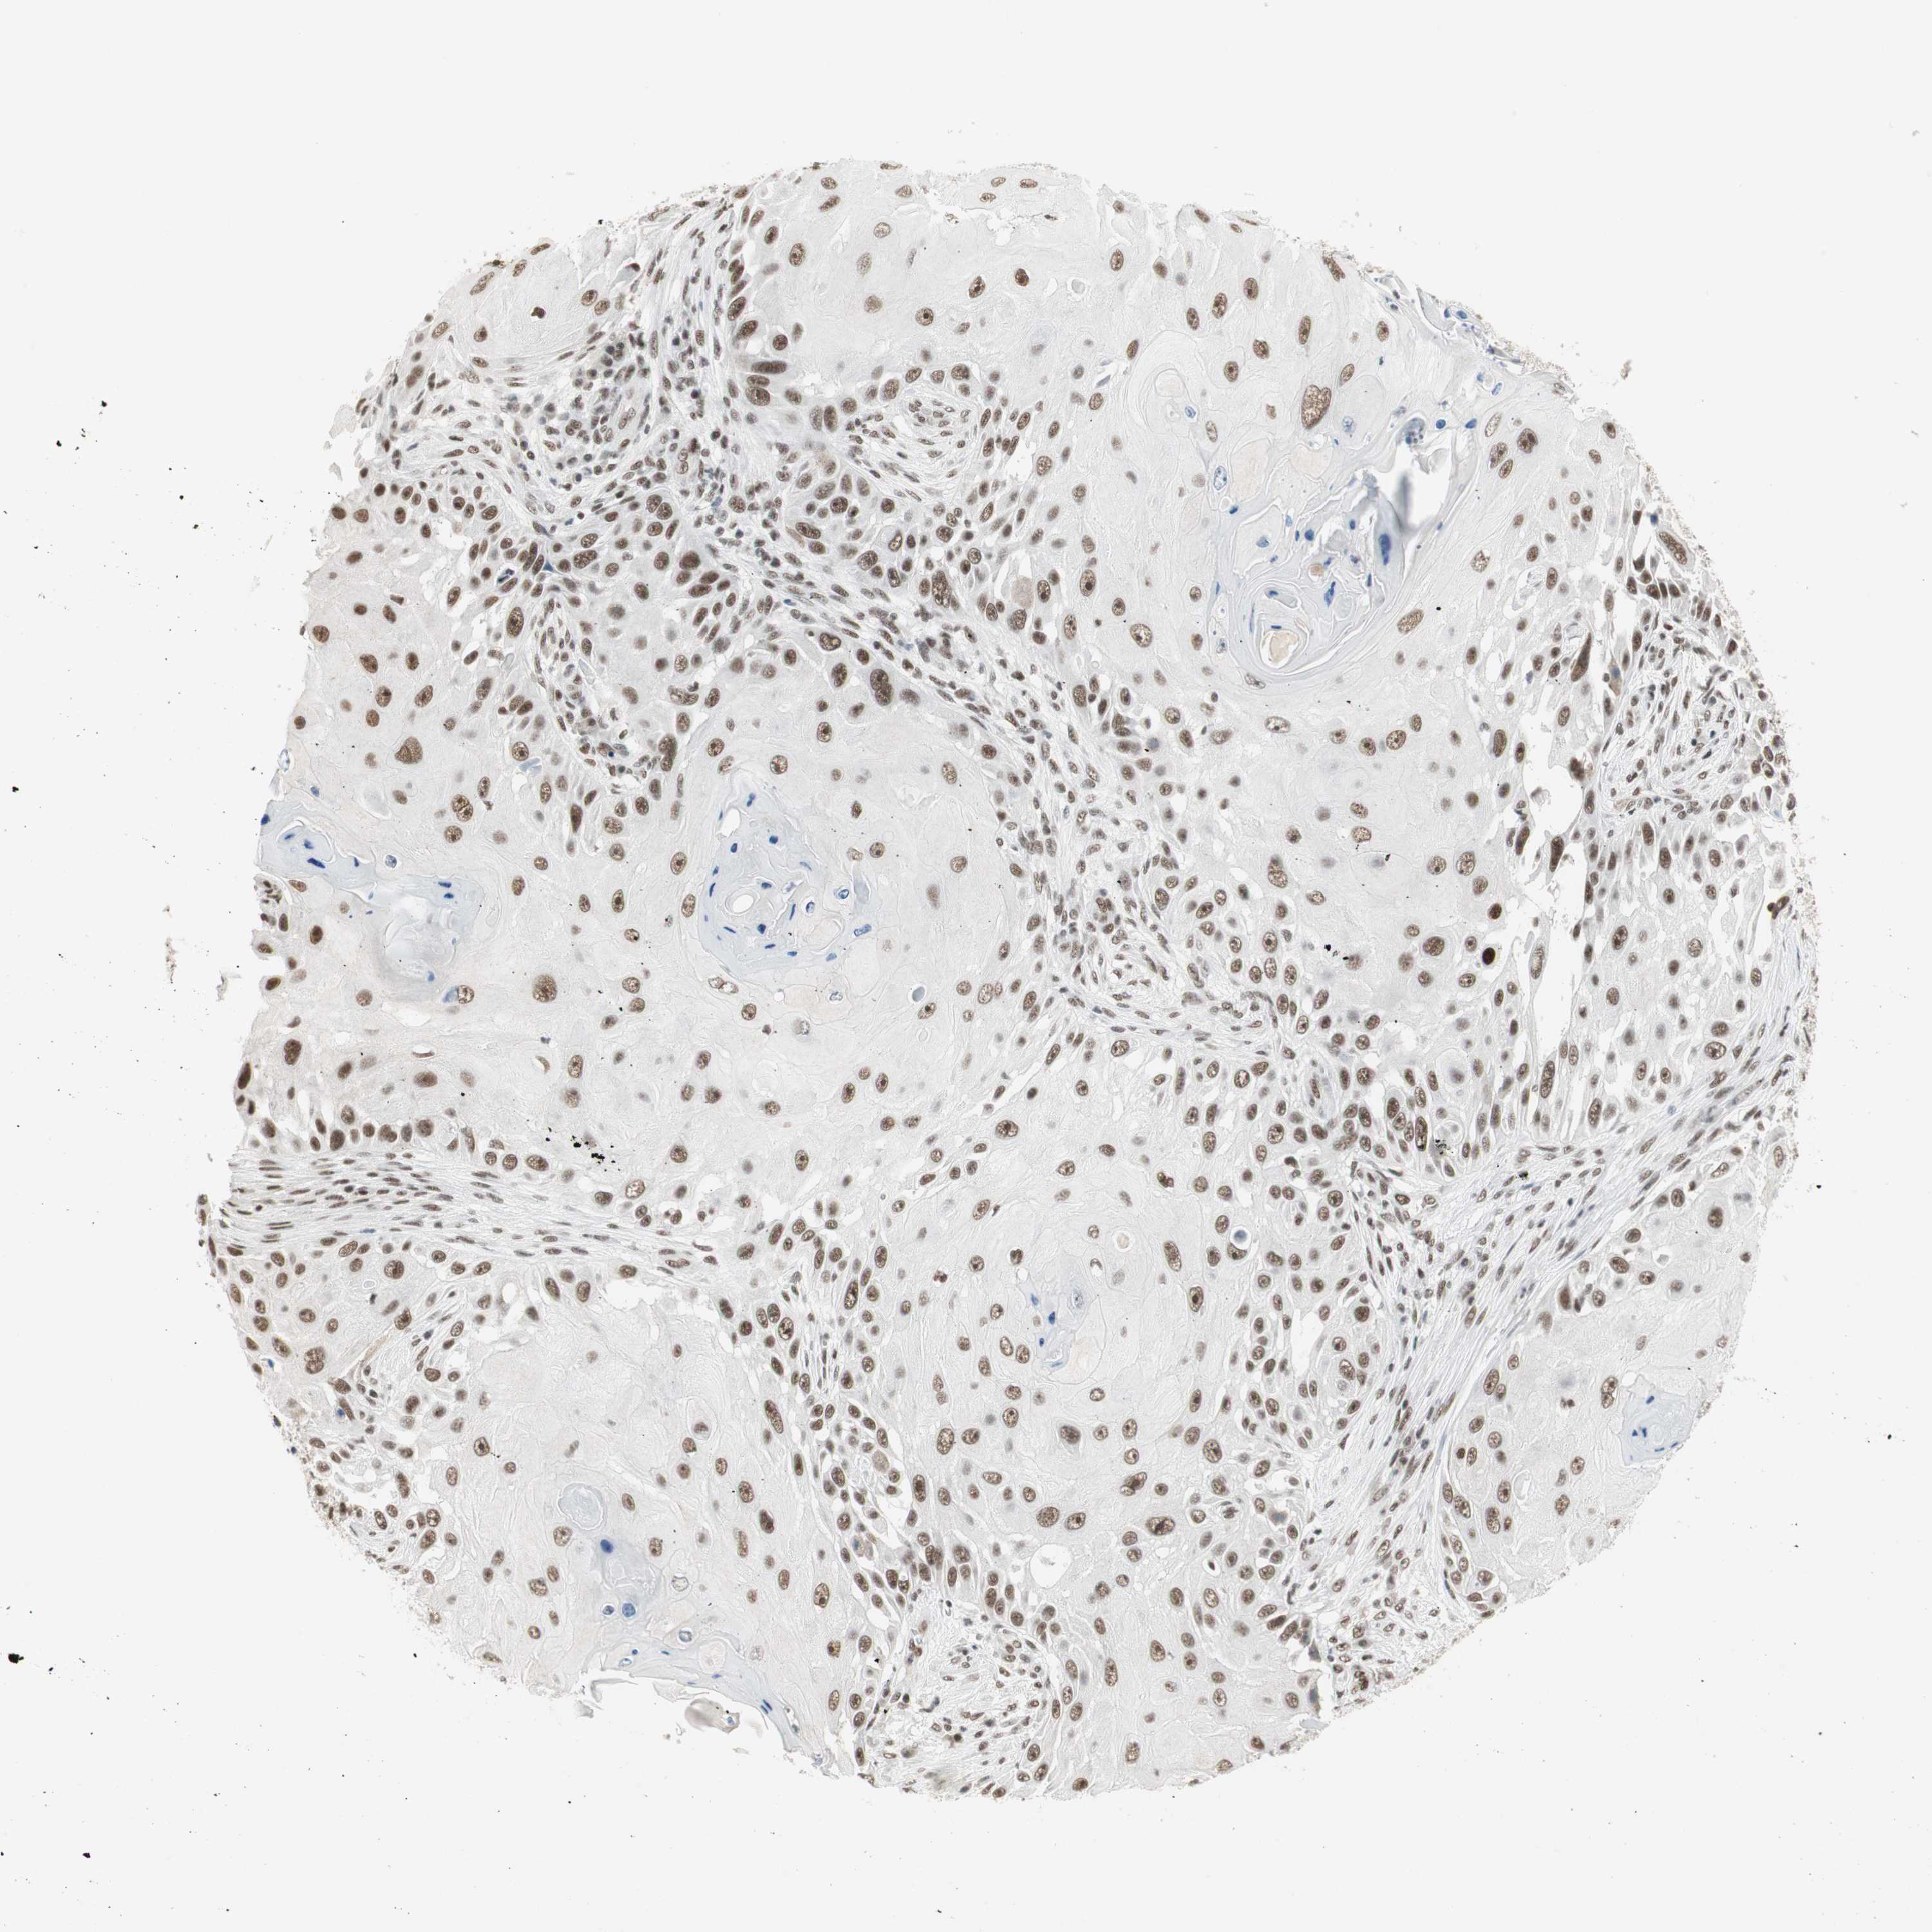

SKIN CANCER - Protein expressioni

A mouse-over function shows sample information and annotation data. Click on an image to view it in a full screen mode. Samples can be filtered based on level of antibody staining by selecting one or several of the following categories: high, medium, low and not detected. The assay and annotation is described here.

Antibody stainingi

Antibody staining in the annotated cell types in the current human tissue is reported as not detected, low, medium, or high, based on conventional immunohistochemistry profiling in selected tissues. This score is based on the combination of the staining intensity and fraction of stained cells.

Each image is clickable and will lead to virtual microscopy that enables deeper exploration of all samples and also displays staining intensity scores, fraction scores and subcellular localization as well as patient and tissue information for each sample.

Antibody HPA006714

Squamous cell carcinoma, NOS